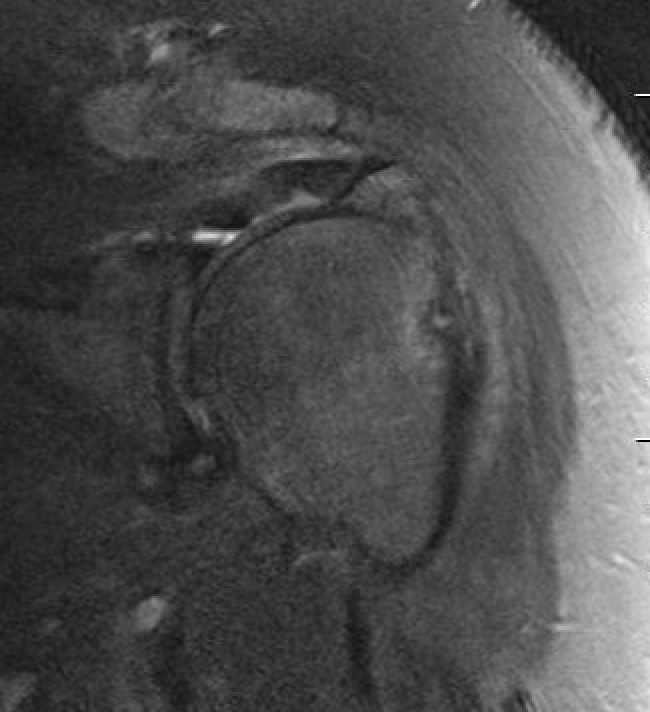

MRI

Displaced GT fracture with torn rotation cuff seen on sagittal MRI